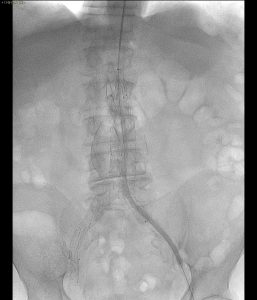

La Sfida Intra-procedurale: L’Occlusione Renale Inaspettata

Durante la procedura è emersa un’insidia improvvisa: l’occlusione dell’arteria renale sinistra. In questi momenti, la capacità di reazione del team e la versatilità degli strumenti endovascolari sono determinanti.

- È stata eseguita una cateterizzazione selettiva attraverso il “free flow” della protesi.

- È stato posizionato con successo uno stent Express LD (6×18 mm, Boston Scientific), ripristinando immediatamente la perfusione dell’organo.